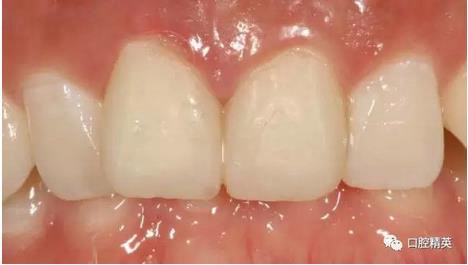

修復體展示

修復體戴入

口內(nèi)正側(cè)位及切端特寫